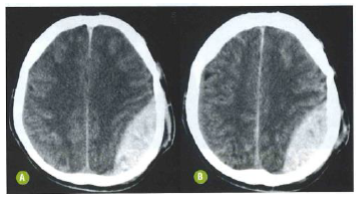

A seguinte tomografia computadorizada de crânio evidencia